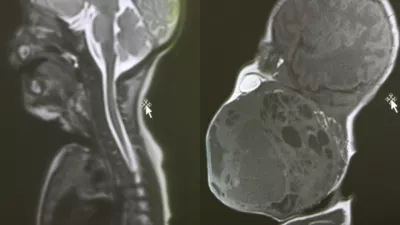

Diagnoza je bila neizprosna: descensus oziroma zdrs medeničnih organov. Njen mehur, maternica in danka so izgubili oporo in se povesili v vaginalni kanal. Spoznanje je bilo šokantno, toda za statistiko presenetljivo običajno.

To namreč ni osamljen primer. Ocenjujejo, da se bo kar 40 odstotkov žensk v svojem življenju srečalo z neko obliko zdrsa medeničnih organov. Gre za stanje, pri katerem podporna tkiva medeničnega dna – mišice in vezi, ki delujejo kot viseča mreža za organe – popustijo. Posledica je zdrs enega ali več organov (mehurja, maternice ali črevesja) navzdol proti vaginalni odprtini.

Težava se lahko začne že pri osnovnem pregledu. Večina ginekoloških pregledov se izvaja v ležečem položaju, kar lahko prikrije resnost stanja. Ko ženska leži, organi zaradi gravitacije zdrsnejo nazaj v notranjost, kar lahko vodi do lažnih negativnih diagnoz ali podcenjevanja stopnje zdrsa.